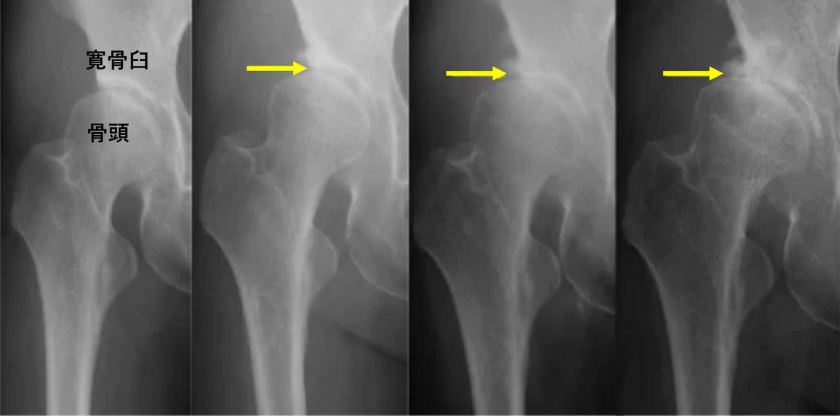

図1 発育性股関節形成不全に伴う変形性股関節症のX線変化(左端は股関節症発症前の発育性股関節形成不全患者のX線写真。右に進むにつれて変形性股関節症が進行している。)